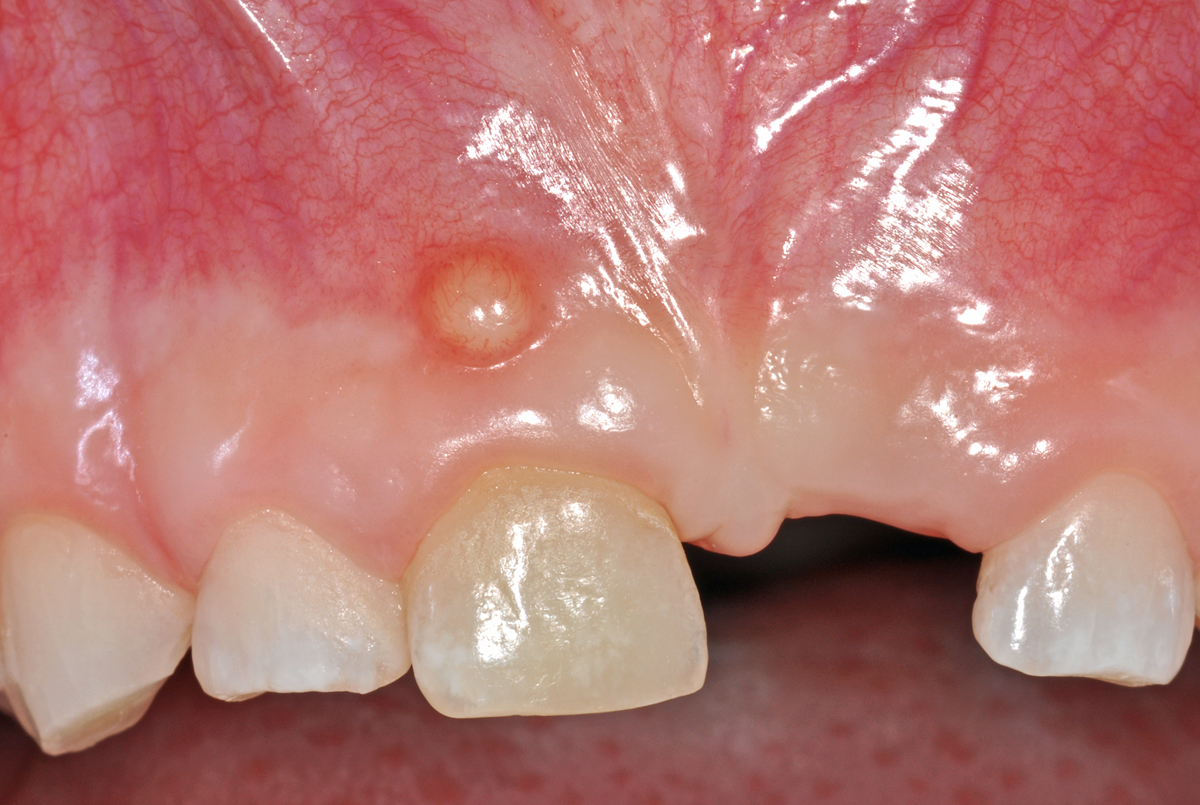

Dieser Fall zeigt einen knapp 7 Jahre alten Patienten, der sich schon vor einiger Zeit bei einem Sturz mit dem Fahrrad den mittleren Milch-Schneidezahn oben links (61) herausgeschlagen hat.

Offensichtlich ist dabei auch der rechte obere mittlere Milch-Schneidezahn (51) in Mitleidenschaft gezogen worden, denn er wurde anlässlich einer Kontrolle ein Jahr zuvor schon als verfärbt notiert (das ist auch auf den Bildern zu erkennen). Bei der neuerlichen Kontrolle zeigte sich an der Mundschleimhaut oberhalb des Zahnes 51 eine kleine, rundliche Erhebung (Pfeil).

Dabei handelt es sich nach klinischer Beurteilung um einen kleinen Abszess (eine eitrige Entzündung), ausgehend vom Zahn 51. In vielen Fällen ist eine solche Entzündung bei Kindern chronisch und verläuft ohne oder mit nur sanftem Schmerz. Oft entleert sich der Eiter dieser Entzündung spontan; man spricht dann von einer Fistel.

Dieser Befund muss durch einen Zahnarzt oder eine Zahnärztin weiter abgeklärt werden – in der Regel werden dazu Röntgenbilder der Oberkiefer-Front angefertigt. Dies dient einerseits zum Erhärten der Diagnose, anderseits auch zum Abschätzen der Notwendigkeit und Dringlichkeit einer Behandlung.